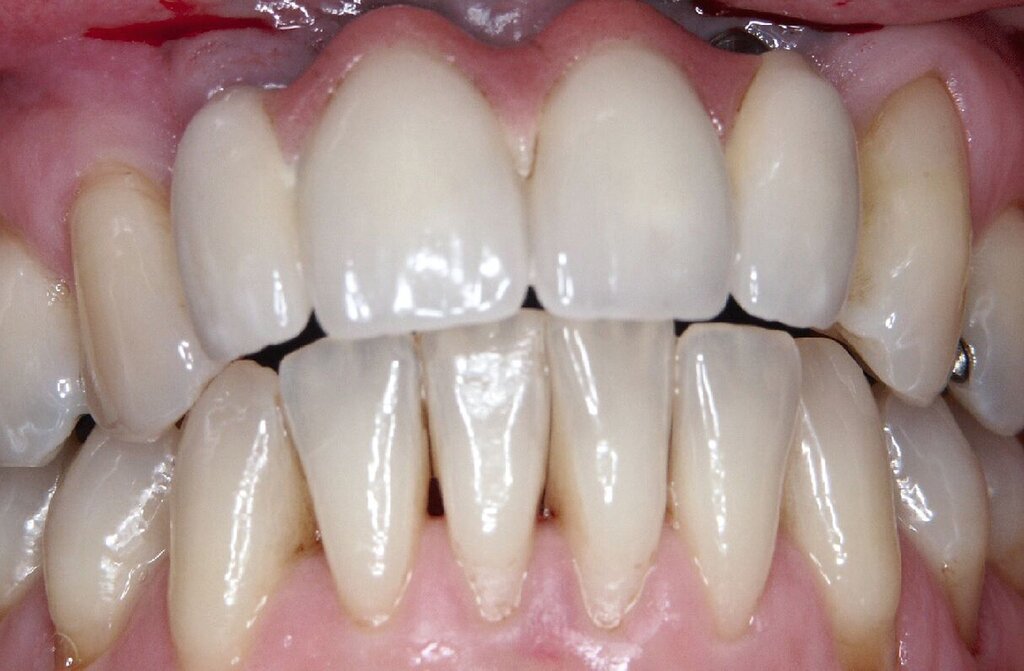

Bei einem 76-jährigen Patienten wurde ein circa 20 Jahre altes Aluminiumoxid-Implantat (Abb. 2a) entfernt, nachdem die ausgeprägte Gingivarezession in Kombination mit dem Abbau der vestibulären Knochenlamelle keine ausreichende Mundhygiene mehr zuließ. Nach Entfernung der Krone auf dem intakten Implantat in regio 11 konnte zur provisorischen Lückenversorgung eine stuhlgefertigte, kombiniert Zahn/Implantat-gestützte Brücke von 011 auf 22 eingegliedert werden (Abb. 2b). Eine Nachimplantation war aufgrund der günstigen Prognose für den Pfeilerzahn 22 überflüssig. Das verbliebene Weichgewebsdefizit wurde drei Monate nach der Explantation mit einem Bindegewebstransplantat vom harten Gaumen kompensiert (Abb. 2c bis 2e). Nach einer Konsolidierungsphase von weiteren drei Monaten wurde das Provisorium durch eine monolithische Zirkoniumdioxidbrücke mit ausschließlich vestibulärer Verblendung ersetzt (Abb. 2g). Eine invasive knöcherne Augmentation mit Wiederherstellung des knöchernen Kieferkamms nach dem Implantatverlust in regio 21 konnte vermieden werden, da eine erneute Implantation für das Behandlungsziel einer festsitzenden Versorgung nicht nötig war.

Da sechs Monate nach der Explantation keine nennenswerte knöcherne Regeneration festzustellen war, wurde eine zweizeitige Implantation nach Knochenaugmentation mithilfe dünner Knochenscheiben aus dem Kieferwinkel geplant. Die Entnahme erfolgte mit oszillierenden Instrumenten (Piezosurgery). Der Knochenblock wurde in dünne Scheiben geschnitten und mit Osteosyntheseschrauben am Alveolarfortsatz fixiert (Abb. 3e). Darüber wurden die Weichgewebe dicht vernäht. Weitere fünf Monate später erfolgte die Schraubenentfernung und die Implantation von zwei Bone-Level-Implantaten in regio 12 und 22 mit geschlossener Einheilung (Abb. 3f und 3g). Bei der Implantatfreilegung weitere sechs Monate später wurden die Weichgewebsdefizite im Brückengliedbereich durch ein kombiniertes Bindegewebs-/Schleimhauttransplantat aufgefüllt und gleichzeitig die keratinisierte periimplantäre Gingiva und Alveloarmukosa verbreitert (Abb. 3h und 3i). Die prothetische Versorgung erfolgte erst weitere drei Monate später, nach dem Konsolidieren der Weichgewebe. Die umfangreichen Augmentationsmaßnahmen konnten das transversale Weichgewebsdefizit vollständig kompensieren, während das verbleibende vertikale Defizit zu zervikal etwas längeren Kronen und Brückengliedern führte. Aufgrund der guten Abdeckung durch die Oberlippe kann das ästhetische Ergebnis als zufriedenstellend bewertet werden (Abb. 3j bis 3l).